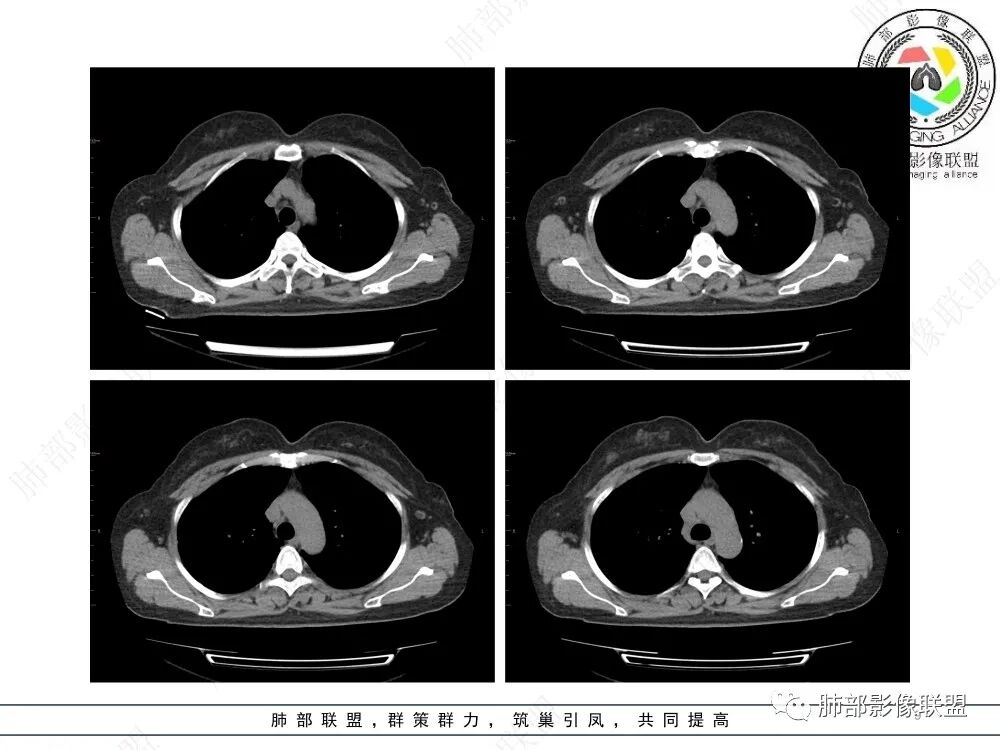

病例特点:52岁女性,体检患者。

影像特点:右肺上叶混合磨玻璃影,边界清晰,结构松散,内有多结节堆积及支气管扩张影,可见小叶间隔增厚,并局部增厚的小叶间隔上亦存在微结节,胸膜侧可见纤细索条,病灶周围可见多发微结节影。

总体分析:从病灶分布来看符合结核的好发位置,影像表现也符合结核的多态性,且出现卫星灶。由于有边界清晰的GGO,需要鉴别腺癌,虽然此病例有边界清晰的GGO,但是它的GGO的边缘有结节感,呈多结节堆积,而腺癌的GGO缺乏这种“多结节堆积感”,另外,此病例也没有发现腺癌的胸膜凹陷征、毛刺征及月牙铲等。